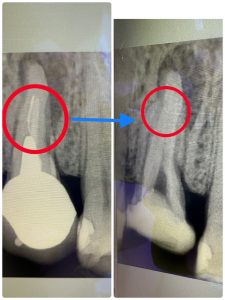

破折ファイル除去

前医で根管治療時に使用する器具が折れてしまい根管の先の方で刺さった状態です。

問題なく経過している場合は除去しなくてもいいのですが、今回は膿が溜まっていた為それを除去する処置をしました。

精密根管治療の中でも最大難易度の治療となります。

治療の経過の写真です。